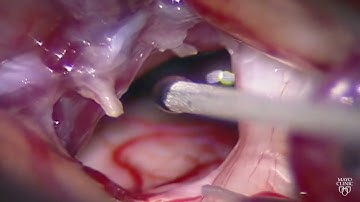

Trigeminal Neuralgia | Causes and Treatment | Part 1